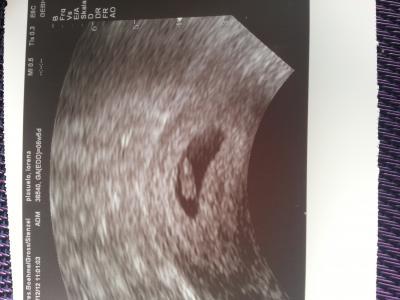

komme gerade vom FA und bin sooo glücklich. bin jetzt 6+5 und entbindungstermin ist der 18.8. das Herz konnte man auch schlagen sehen. meinen mutterpaSs hab ich nun auch. bin so Happy :)

Bild zu zurück vom FA :) - Forum für August - Mamis